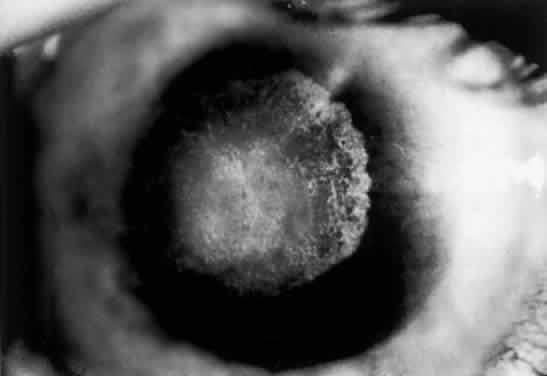

OCULAR FINDINGS. One of the few truly diagnostic and pathognomonic physical signs in clinical medicine is a Kayser-Fleischer corneal pigment ring found in patients with Wilson's disease (Fig. 5).This ring is recognized as a golden-brown, ruby-red, or green band of 1.0 to 3.0 mm, starting at the limbus but at the level of Descemet's membrane.53 The color of the ring is presumably caused by scattering and reflection of incident light and by photointerference effects created by the layers of copper granules. Such variables as size, shape, and unit density of the granules may account for the different appearances of the Kayser-Fleischer ring. The course of the Kayser-Fleischer ring has been well documented.54,55 The site of earliest pigment deposition is an arc in the superior periphery of the cornea from the 10- to 2-o'clock meridian. The arc spreads slowly toward the horizontal plane and gradually broadens. Later in the progression of the ring formation, a band appears inferiorly as a crescent stretching from the 5- to 7-o'clock positions. In time, the two arcs meet. With treatment, the sequence of events is reversed, and after the copper has reabsorbed, a pitted or beaten silver pattern may become apparent at the previous site of the ring. This is an indication that treatment has produced a negative copper balance.49 Decreased visual acuity is not a problem. Rarely, copper is deposited in the crystalline lens, giving an anterior subcapsular “sunflower” cataract.

Fig. 5. Wilson's disease. Kayser-Fleischer peripheral corneal ring. Copper pigment at level of Descemet's membrane.